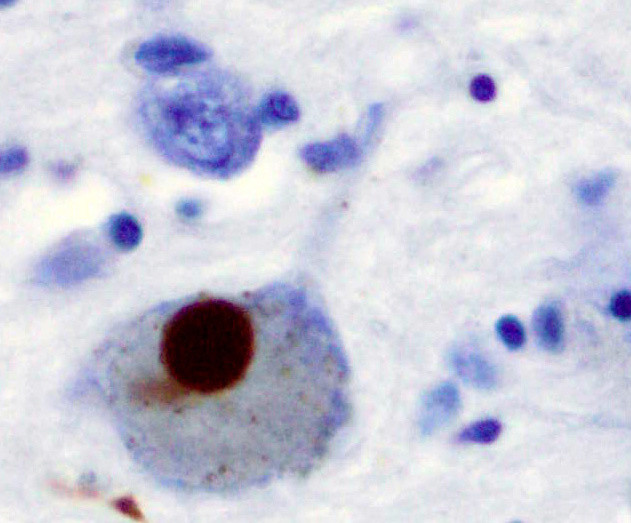

Тельца Леви, окрашенные по альфа-синуклеину

Нейродегенеративные заболевания, такие как болезнь Паркинсона, Альцгеймера и прионные инфекции, во многом связаны с накоплением в мозге неправильно свернутых белков, образующих токсичные амилоидные агрегаты. Особый интерес для науки представляет взаимодействие между разными классами таких белков, например, прионного белка (PrP) и альфа-синуклеина (α-syn), ключевого игрока в развитии болезни Паркинсона. Однако данных о таких взаимодействиях накоплено недостаточно, и они зачастую противоречивы.